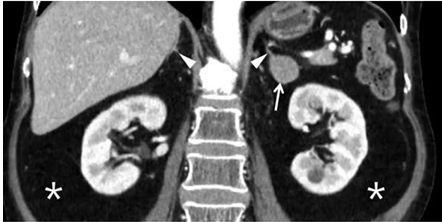

Observe atentamente a imagem e escolha a opção que completa os espaços pontilhados de forma correta. A imagem de nódulo em adrenal esquerda (apontado pela seta) identificado por_____________ sendo a função da glândula suprarrenal a ativação__________.